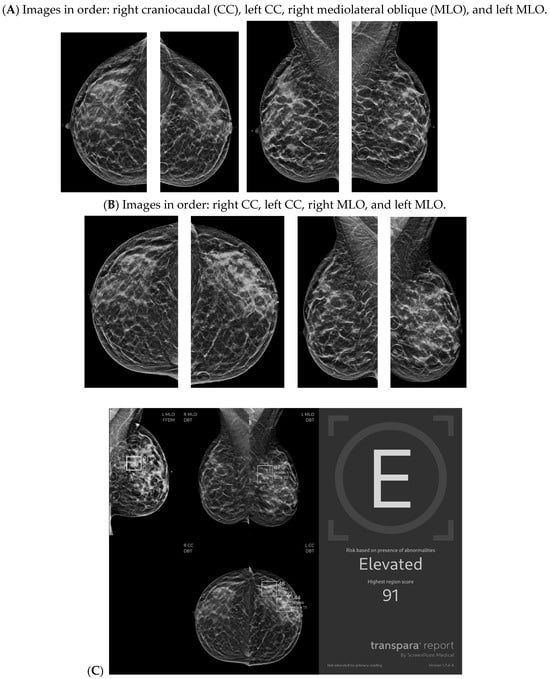

With the widespread implementation of DBT, which increases mammographic cancer detection sensitivity, there are larger volumes of images. This may ultimately increase the risk of reduced accuracy, perhaps due to reader fatigue and increased reading time [24]. There are numerous tomosynthesis AI products available, and at our institution we have implemented the use of Transpara, which is a deep learning-based AI system that uses deep CNN to help improve early-stage cancer detection and sensitivity (at similar specificity), while reducing reading time [24,25]. We view tomosynthesis AI as a valued asset to our clinical practice, as the software highlights potential areas of concern that require additional attention (Figure 1 and Figure 2). However, some areas flagged as concerning are often classically considered benign, such as stable post-lumpectomy sites, stable asymmetries and calcifications, or previously biopsied benign findings. That being said, tomosynthesis AI has been found to have a synergistic effect on cancer detection rate (CDR) when utilized by the radiologist. A study found that radiologist-only CDR was 67.3% and AI-only CDR was 72.7%, but when the radiologist and AI software were used together, the CDR increased to 83.6% [17,25,26]. Lunit INSIGHT MMG, Seoul, South Korea was the diagnostic support software used in this particular study [26].

Figure 1.

Developing asymmetry detected by artificial intelligence (AI): Between the baseline screening mammogram (A) and the follow-up screening mammogram 17 months later (B), there has been a very subtle development of left breast asymmetry that is difficult to perceive with the naked eye. However, the AI program Transpara highlighted potential regions of interest (C) for the radiologist to query for additional mammographic and sonographic imaging. On further diagnostic imaging, the subtle asymmetry corresponds to a hypoechoic mass at left 4:00, 3 cm FN (D) with hypervascularity (E). AI program Koios correctly recognized the mass as “Probably Malignant”, and this area returned as a biopsy-proven invasive malignancy with lymphangitic spread (F). Images obtained from the Icahn School of Medicine at Mount Sinai.